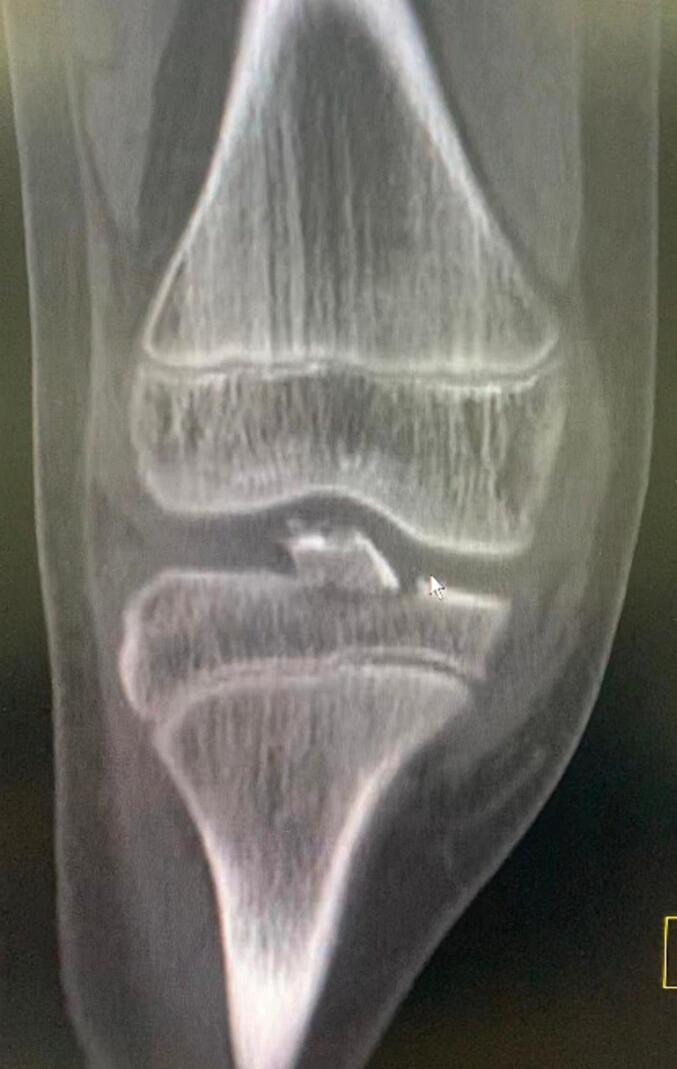

Distal anterior cruciate ligament avulsion from tibial side is an unusual injury. It can be either bony avulsion, which is more common, or rarely a soft tissue peeling of tibial spine with no bone injury. This case report represents a very infrequent injury of combined soft tissue peeling of distal anterior cruciate ligament along with bony avulsion of tibial spine in a 12-years-old boy after falling from his bike.

前交叉韧带从胫骨侧远端撕脱是一种不常见的损伤。它可以是较为常见的骨性撕脱,或者极少情况下是胫骨棘的软组织剥离且无骨质损伤。本病例报告呈现了一名12岁男孩从自行车上摔下后,前交叉韧带远端合并软组织剥离及胫骨棘骨性撕脱这种非常罕见的损伤情况。